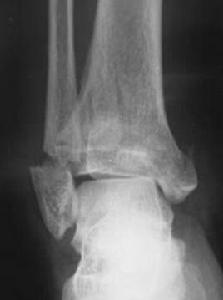

外傷後踝部腫脹、畸形、不能負重,追問受傷時的情況來判斷是否有軸向暴力發生作用。結合X線片或CT檢查,Pilon骨折的診斷並不困難。X線片包括:(1)踝關節正、側位像;(2)外鏇斜位像,可很好地顯示脛骨前內側和後外側關節面骨折情況;(3)對側踝關節X線片,既可以排除骨折的存在又可以作為復位的模特。CT片能夠很好的顯示骨折的形態、骨折塊的數量以及移位的程度,矢狀位和冠狀位重建圖像能夠顯示出事實上更為複雜的骨折情況。在評價骨折的移位程度、術前制定的治療方案以及指導手術治療方面,CT較普通X線片有明顯的優勢。